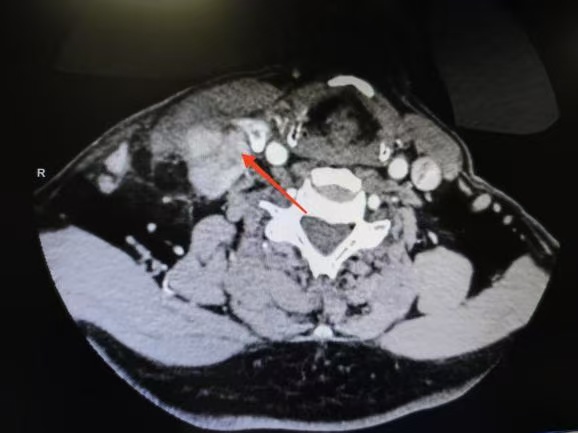

CT箭頭所示:側(cè)頸區(qū)轉(zhuǎn)移淋巴結(jié)

針對患者危急情況,甲狀腺乳腺外科迅速組建由沈浩元副主任醫(yī)師,楊青青主治醫(yī)師、王放明住院醫(yī)師的手術(shù)診療團隊。經(jīng)過4小時精細操作,團隊完整切除雙側(cè)甲狀腺及腫瘤,并完成中央?yún)^(qū)與頸側(cè)區(qū)淋巴結(jié)根治性清掃,成功保留了對發(fā)聲功能及血液循環(huán)至關(guān)重要的喉返神經(jīng)與頸內(nèi)靜脈。目前患者恢復順利,已轉(zhuǎn)危為安,診療效果得到患者及家屬認可。